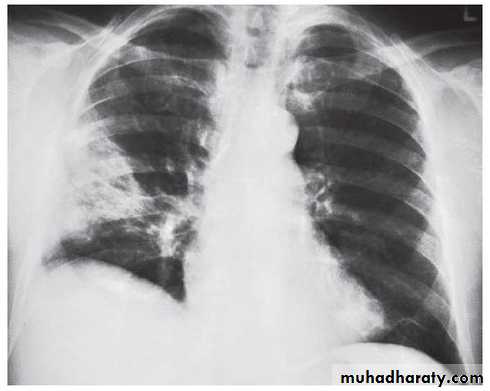

BRONCHOPNEUMONIA

Mycoplasma pneumonia. A 35 year old man presents with nonproductive cough and fever